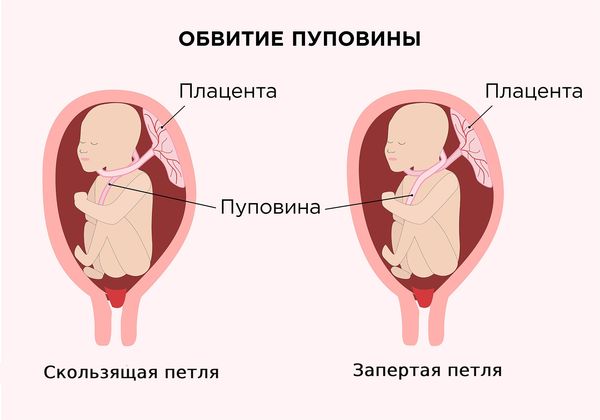

По типу обвития выделяют:

- Тип А. Плод закручивается в пуповину как будто укутывается шарфом (скользящая петля).

- Тип Б. Обвитие похоже на незавершённый истинный узел (запертая петля). Другое название — незавершённое узлообразование.

Типы обвития пуповиной

На 50 случаев типа А приходится 1 случай типа Б. Обвитие типа А может самостоятельно распутаться. [1]. Обвитие типа Б само не распутывается, его снимает с шеи акушер после рождения головки плода. Такие роды проводятся в обычных родильных домах.